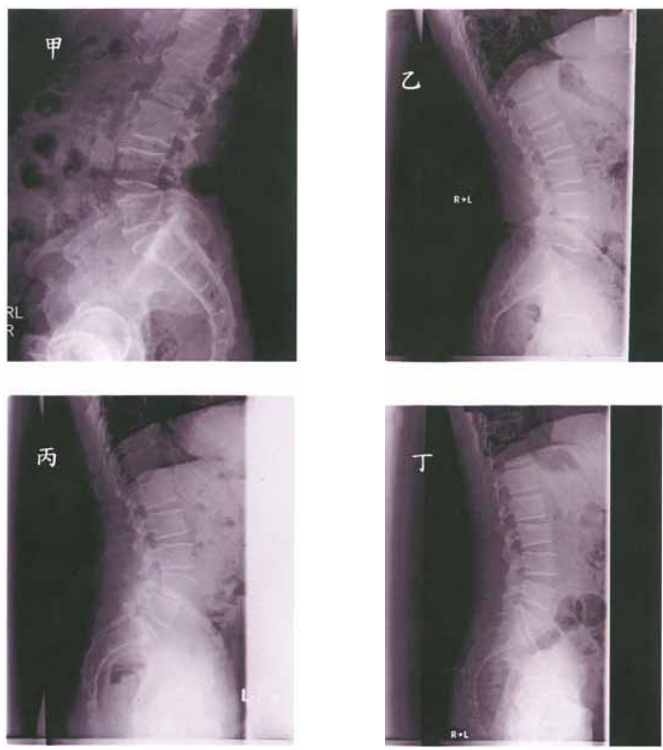

21 如圖所示之 3 種股骨頸骨折,其中圖甲傾斜角 30°,圖乙傾斜角 45°,圖丙傾斜角 70°,試問:何者 較穩定,血循破壞較少,故癒合率較高?

(A)甲 (B)乙 (C)丙 (D)都一樣

23 下列 4 位脊椎的病變中,何者最屬急性之傷害?

(A)甲 (B)乙 (C)丙 (D)丁